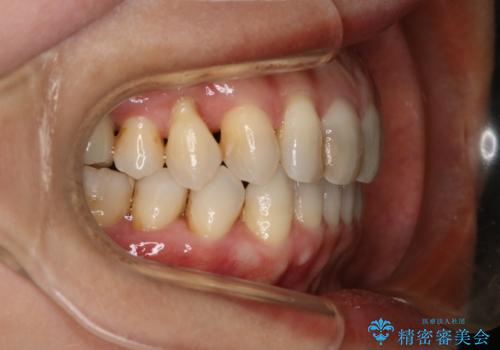

90度捻じれてしまい、完全にはみ出している歯を抜かずにインビザラインで治す。一般治療もできる精密審美会だからこその治療

- 右上の小臼歯が二本とも90度捻じれてしまっており、奥歯の噛み合わせに問題が生じていました。

歯を抜いてワイヤー治療を行うという選択肢もありましたが、

奥歯の被せ物の形を適切にすることで非抜歯でも治療が可能であると判断し、

非抜歯、インビザラインでによるマウスピース矯正治療を行うことにいたしました。